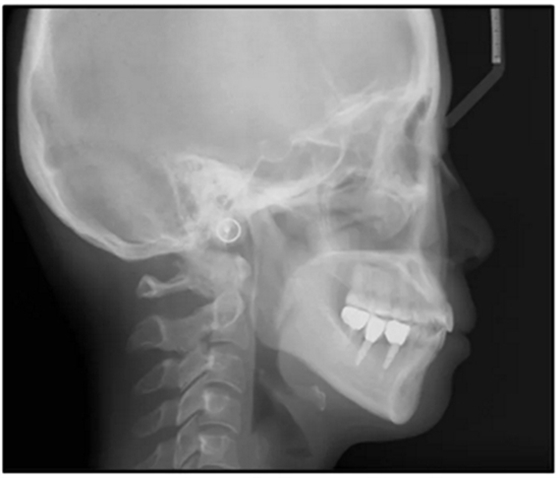

36歲;女性;尋求下頜左后方區(qū)域間隙管理的建議(圖1和圖2),通過治療獲得了良好的牙頜面效果(圖3和圖4)。她被診斷患有骨性I類和代償性牙性II類錯合畸形,并且上頜左側尖牙缺失(圖1和2)。大約七年前,由于不可修復的齲齒,拔除了下頜左側第一和第二磨牙(圖5)。37相鄰的第三磨牙向近中移動并傾斜入間隙,導致無牙頜間隙減小至約14 mm(圖2和圖5)。臨床和影像學評估顯示多發(fā)性齲損和在下頜右側567處有一不良的固定橋修復體(圖1和5)。此外,下頜左中切牙缺失,造成下頜中線向左側偏移約3 mm(圖1和圖2)?;颊咦栽V,她的右上第一前磨牙和左上尖牙在13歲時由其家庭牙醫(yī)拔除,因為它們被阻塞到頰側萌出(圖1)。上頜第二磨牙缺失(未知病因),并且相鄰的第三磨牙已經(jīng)轉移到第二磨牙間隙中。如補充材料所示,美國正畸學差異指數(shù)DI是28分。種植體部位(下頜左側和右側第一磨牙)由于復雜性得到額外4分(補充材料)。

圖5. 治療前的側位片(上圖)和全景(下圖)的X光片

治療選擇

修復下頜左側缺牙區(qū)的第一種方法是增加牙槽嵴骨量并植入2顆種植體。然而,這樣就要增加一個植體,且手術難度大,效果難以預測,因為缺牙區(qū)的牙槽骨嚴重不足。此外,因為左側下頜第三磨牙的近中傾斜(圖5),第三磨牙與種植體之間易形成食物嵌塞和牙菌斑積聚,有引起長期的牙周問題,如牙周炎或種植體周圍炎的風險。第二種選擇是用可摘局部義齒替代缺失的下頜骨左側磨牙,但第三磨牙的近中傾斜可能會影響義齒的就位道。解決這個問題,需要拔除第三磨牙或進行修復,使磨牙有一個符合標準的牙冠?;颊哂捎陬~外的外科手術,原第三磨牙無法完全發(fā)揮功能,牙周風險加劇,拒絕了這兩種可選擇的治療方法。